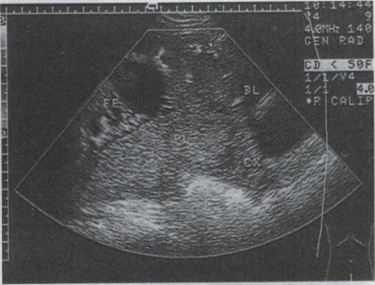

41.女,25岁,停经33周。阴道无痛性出血2天。B超检查如图,最可能的诊断为()